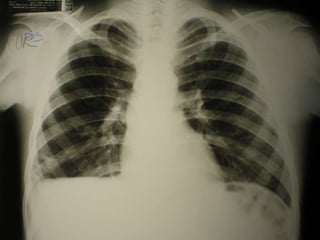

Caso Clínico 1

08/08/2003- p=46kg,PA=120X60mmHg, edema abdominal e oligúria=800mL/dia. Hemácias 5.820.000/mm 3 Hb 16,9g% Htc 51,3% Leucócitos 15400/mm 3 B 2 S 63 L 31 L reat 2 Plaquetas 490.000 Uréia 49 Creatinina 0,4 Na 129 K 3,9 Cl 106 PCR <6mg/dl EAS: pH 5,0 d 1,025 Proteína +++ Piócitos 2/campo Glicose ausente Hemácias raras Corpos cetônicos ausente Epitélios raros Hemoglobina ausente Muco + Nitrito negativo Bactérias ligeiramente elevadas Cilindros: raros cilindros hialinos e raros cilindros granulosos 09/08/2003- p=47kg, PA=100x80mmHg, oligúria=500mL/dia 10/08/2003- Proteinúria 24 horas: 0.96, p=47,5k, PA=110x60,diurese=1060mL/dia

08/08/2003-  p=46kg, PA=120X60mmHg, edema abdominal e oligúria=800mL/dia.  Hemácias 5.820.000/mm 3 Hb 16,9g% Htc 51,3% Leucócitos 15400/mm 3 B 2  S 63  L 31  L reat 2 Plaquetas 490.000 Uréia 49 Creatinina 0,4 Na 129  K 3,9  Cl 106   PCR <6mg/dl EAS: pH 5,0 d 1,025 Proteína +++ Piócitos 2/campo Glicose ausente Hemácias raras Corpos cetônicos ausente Epitélios raros Hemoglobina ausente Muco + Nitrito negativo Bactérias ligeiramente elevadas Cilindros: raros cilindros hialinos e raros cilindros granulosos 09/08/2003-  p=47kg, PA=100x80mmHg, oligúria=500mL/dia 10/08/2003-  Proteinúria 24 horas: 0.96, p=47,5k,  PA=110x60,diurese=1060mL/dia